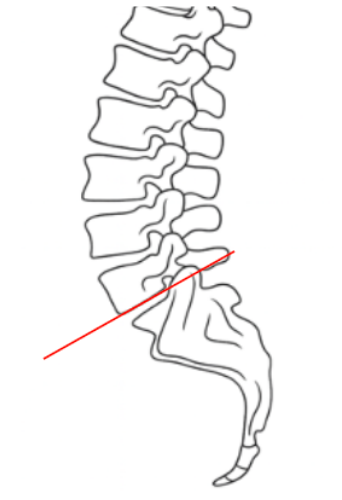

McNab’s Line is a radiographic assessment of the lumbosacral junction alignment, specifically evaluating the angular relationship between the inferior endplate of L5 and the superior surface of S1.

• Draw a tangent line along the inferior endplate of L5.

• Assess for intersection with the superior surface of the sacrum

• Intersection suggests spondylolysis

• Normal segmental alignment: tangent line does not cross superior surface of sacrum; physiologic lumbosacral lordosis

• Hyperlordotic segment: tangent line crosses posterior portion of superior surface of sacrum; often compensatory in anterior shear (spondylolisthesis)

• Hypolordotic/flat segment: tangent line crosses anterior portion of superior surface of sacrum; suggests disc height loss, segmental kyphosis, or early instability